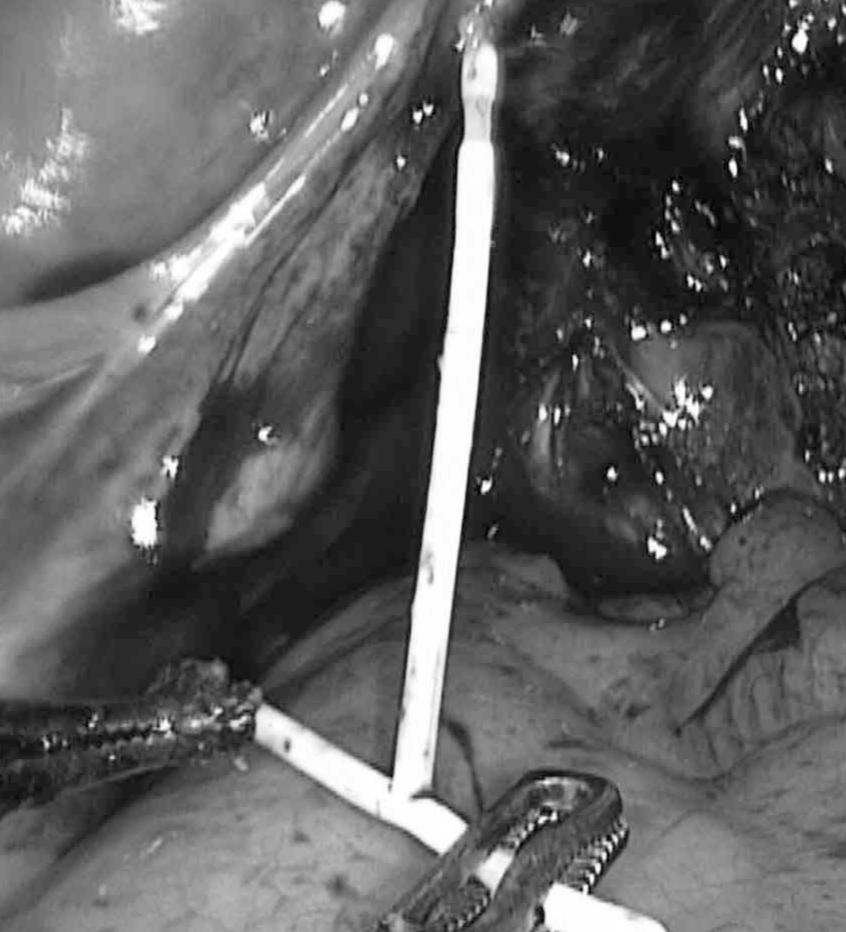

腹腔镜探查:子宫后位,萎缩;直肠前壁、子宫后壁及双侧子宫骶韧带致密粘连(刚进腹的时候连环的“影子”都看不到。

好在准备充分,结合术前的CT片及术中情况,以超声刀、剪刀逐渐分离开肠管与子宫后壁之粘连后,我们发现了肠子表面有一小片白色异物,没错,就是它了!

经过耐心的分离,“T”型环终于暴露出来了:原来它其中的一端短臂暴露在直肠表面,而长臂及另一端短臂全部扎入直肠前壁内。我们用抓钳夹住节育环后,以最小损伤肠管的方式将它从肠子里“揪”了出来,并将肠子进行了修补。

让我们一起来看看“T型”环被揪出来的瞬间吧~

环取出前

环取出后